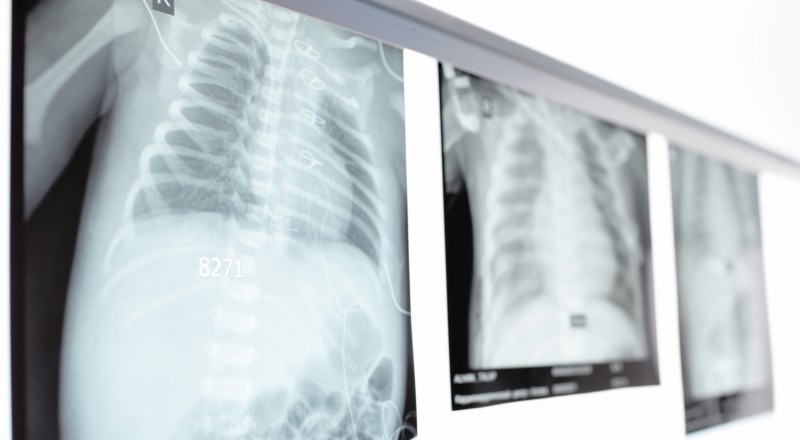

مرض السل – مرض معدي ينتقل بواسطة رذاذ التنفس، وفي حالة عدم معالجة الشخص المصاب يمكن ان يعدي يوميا 10 – 15 آخرين. يقضي هذا المرض حاليا على حياة 1.6 مليون انسان سنويا، أغلبهم من سكان البلدان النامية.